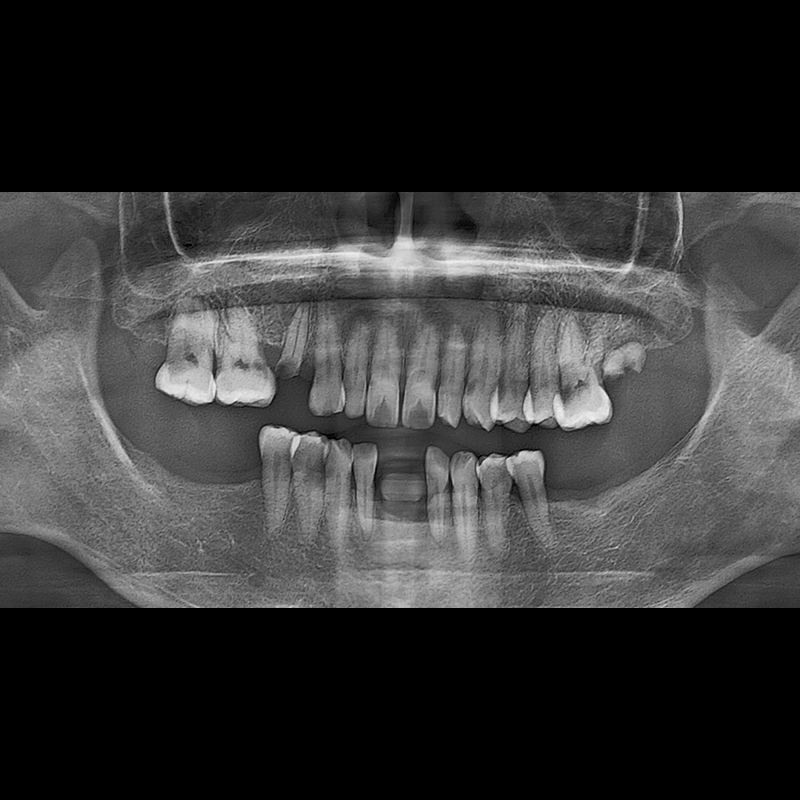

BEFORE AFTER

种植牙前后的照片 2025.05.30

在缺失的牙齿部分和难以挽救的牙齿位置植入了种植牙。